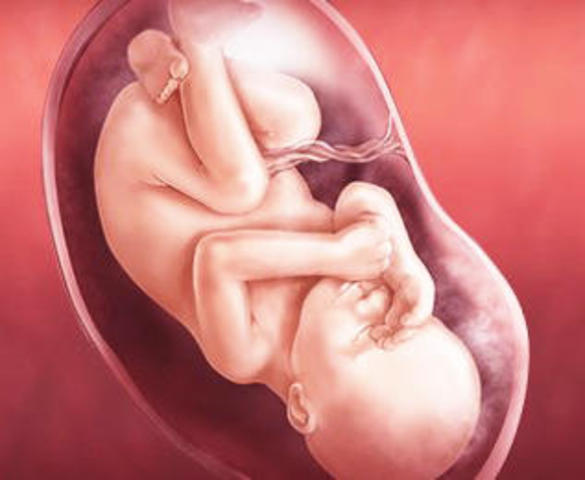

• Semana 39 y 40

Semana 39 y 40

Cada vez tiene menos espacio para moverse dentro del útero. Ya están maduros todos los órganos y en cualquier momento puede producirse el parto.Desde hace semanas, el bebé alterna periodos de vigilia y de sueño. Aunque apenas dispone de espacio, sus movimientos son vigorosos. Tiene los rasgos faciales bien definidos.La cabeza del producto está encajada en la pelvis materna y sus huesos craneales son flexibles para adaptarse al canal del parto.